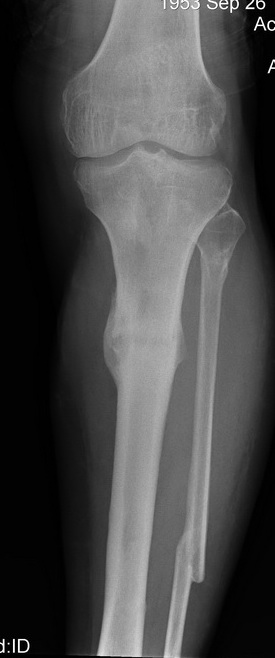

2. С аппаратом и резекцией малоберцовой кости все понятно, но почему вы предполагаете значимое укорочение, требующее транспорта? В моем случае есть признаки формирования нормотрофического (по крайней мере не аваскулярного несращения)- в приложении боковая рентгенограмма.

Качество остеосинтеза (по центрированным снимкам)я расцениваю как удовлетворительное.

Итак - удалили стержень, воспалительный процесс к тому моменту купирован, наложили кастовую повязку и в течение 3 месяцев на контрольных рентгенограммах - признаки консолидации. Уже в сентябре, т.е черз 5 месяцев после нагноения пациент вернувшиь с подвождной охоты привез здорового сазана - основная жалоба - ноги побаливают после длительного лпаваня в ластах. Прилагаю снимки через год после удаления стержня. Вот такая, на этот раз счастливая казуистика.